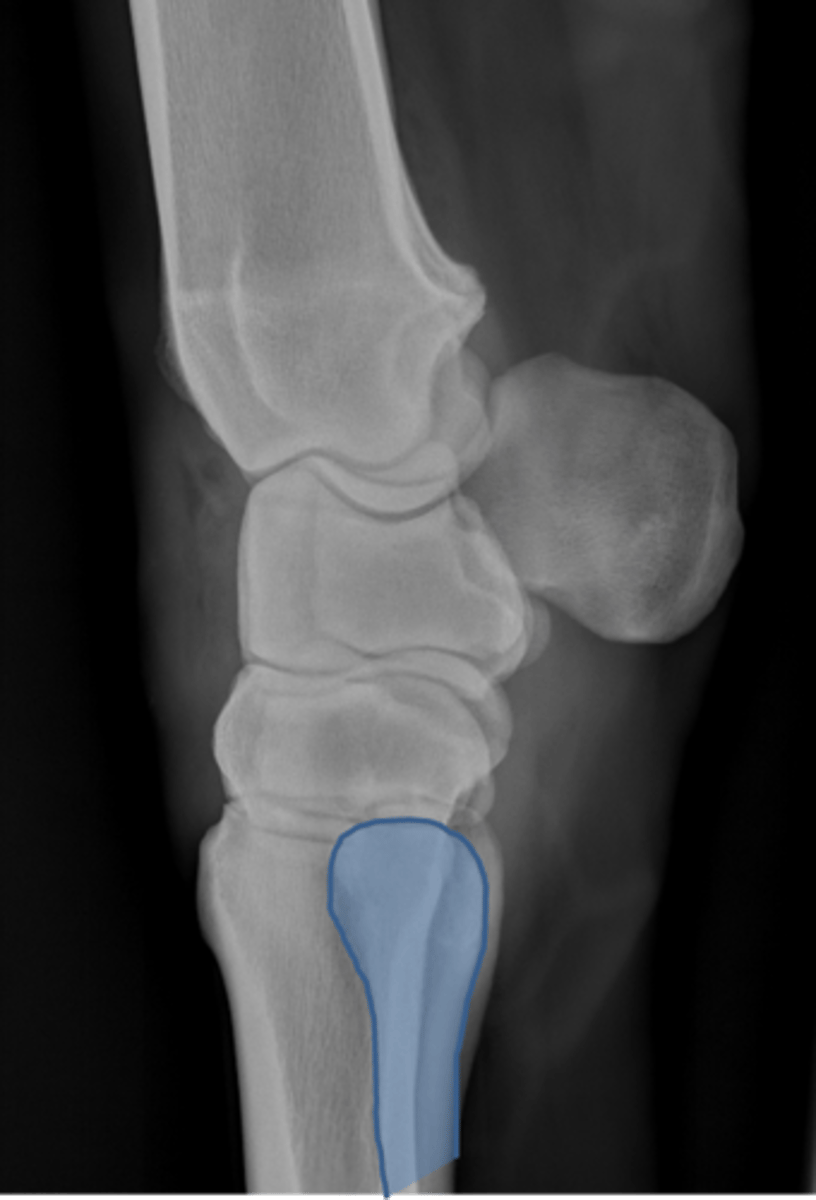

Carpus, lateral

ID joint and view

Antebrachiocarpal joint

Middle carpal joint

Carpometacarpal joint

Radial carpal bone

Intermediate carpal bone

Ulnar carpal bone

Third carpal bone

Second carpal bone

Fourth carpal bone

Accessory carpal bone

Second metacarpal (medial splint)

Fourth metacarpal (lateral splint)

Cannon bone